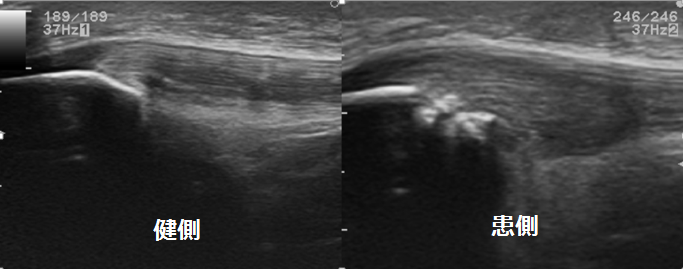

同部位を超音波エコーで観察してみました。健側(正常な膝)と比べると、ずいぶん腫脹しているのがわかると思います。

また、痛みが現れてから時間が経過しているためか、腱の部分だけではなく膝蓋骨にも不整な変化が見られます。

この症例の場合、膝蓋腱の深層における変化がとらえられます。